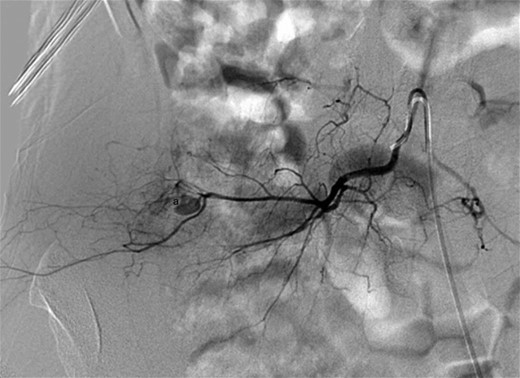

Digital subtraction angiography demonstrating successful embolization of the proximal and distal entry points of the pseudoaneurysm using platinum microcoils (a).